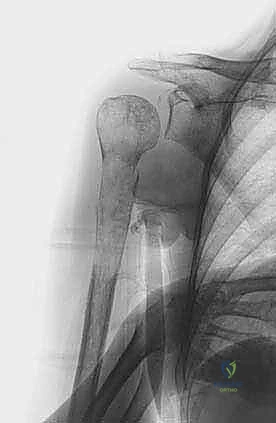

3. الاستئصال الجذري والمفاصل الصناعية الخاصة بالأورام (Tumor Endoprosthesis)

في حالات التدمير الواسع جداً للعضد القريب (قرب الكتف) أو العضد البعيد (قرب الكوع)، أو في حالة النقيلة الوحيدة التي تتطلب استئصالاً جذرياً (En-bloc resection) لضمان عدم عودة الورم:

* يقوم الدكتور محمد هطيف باستئصال الجزء المصاب من العظم بالكامل مع الورم المغلف به ككتلة واحدة، بهوامش أمان سليمة.

* يتم استبدال العظم والمفصل المستأصل بـ مفصل صناعي ضخم خاص بالأورام (Modular Megaprosthesis). هذه المفاصل مصنوعة من التيتانيوم والمعادن المتقدمة، وتأتي بقطع قابلة للتركيب لتناسب الطول الدقيق للعظم المفقود.

* هذه الجراحة تتطلب مهارة فنية عالية جداً لإعادة خياطة العضلات والأوتار (مثل أوتار الكفة المدورة في الكتف) في المفصل الصناعي لضمان عودة حركة الذراع.